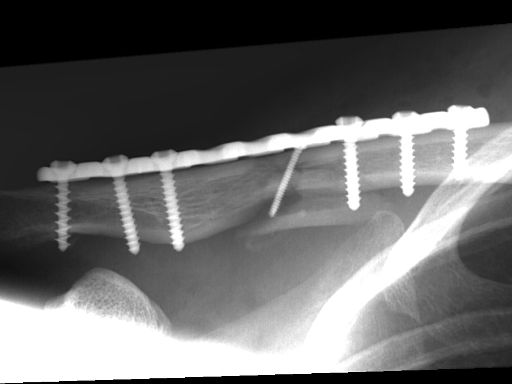

Clavicula-Fraktur (23./25. Juli/2. August 2007)